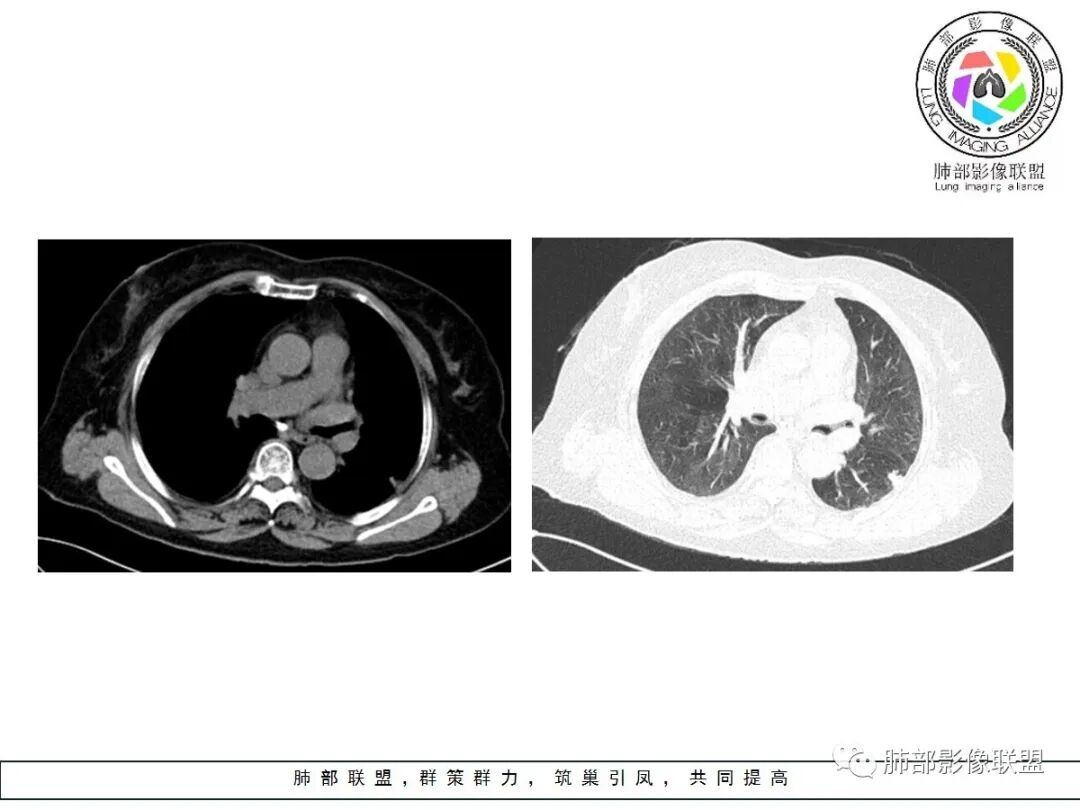

边缘平直

宽基底与胸膜相连

3.病灶显著强化不支持结核;边界清楚,肺门一侧波浪状改变,患者为老年女性,缺乏临床表现,尽管影像有一些炎性灶特点,但恶性肿瘤性病变不能除外。

二、早期结节型粘液腺癌诊断是腺癌诊断的难点之一,有哪些特点提示我们呢?根据曹悍波老师视频的总结如下:

1.中老年女性多见,单发,发病部位常位于双肺下叶胸膜下或叶间胸膜下,考虑与粘液重力分布有关。

2.50%左右为圆形,表现为椭圆形的结节生长方向与支气管垂直,其他的为不规则形,大部分病灶具有一定的恶性征象,少数不典型。

3.表现为混合磨玻璃结节,边界似清非清,为粘液向外飘散;实性结节收缩力弱,是由于粘液张力抵消了一部分纤维的收缩力,由于生长的不对称常导致收缩力不对称。

4.粘液腺癌的破坏力相对较低,血管及支气管破坏轻,可见血管造影征及空气支气管征;侵袭力弱,发展慢。

5.部分病灶需要与炎性病变、良性结节相鉴别,因此,临床抗炎治疗和短期随诊复查是非常必要的。